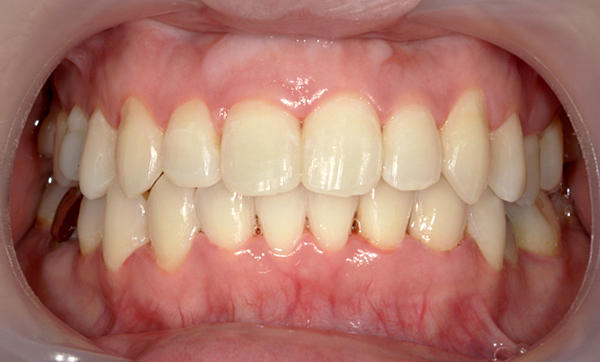

症例_009 「上下の前歯」症例

治療期間:7ヶ月金額:54万円+税20代女性捻転歯一部の反対咬合前歯のガタガタ